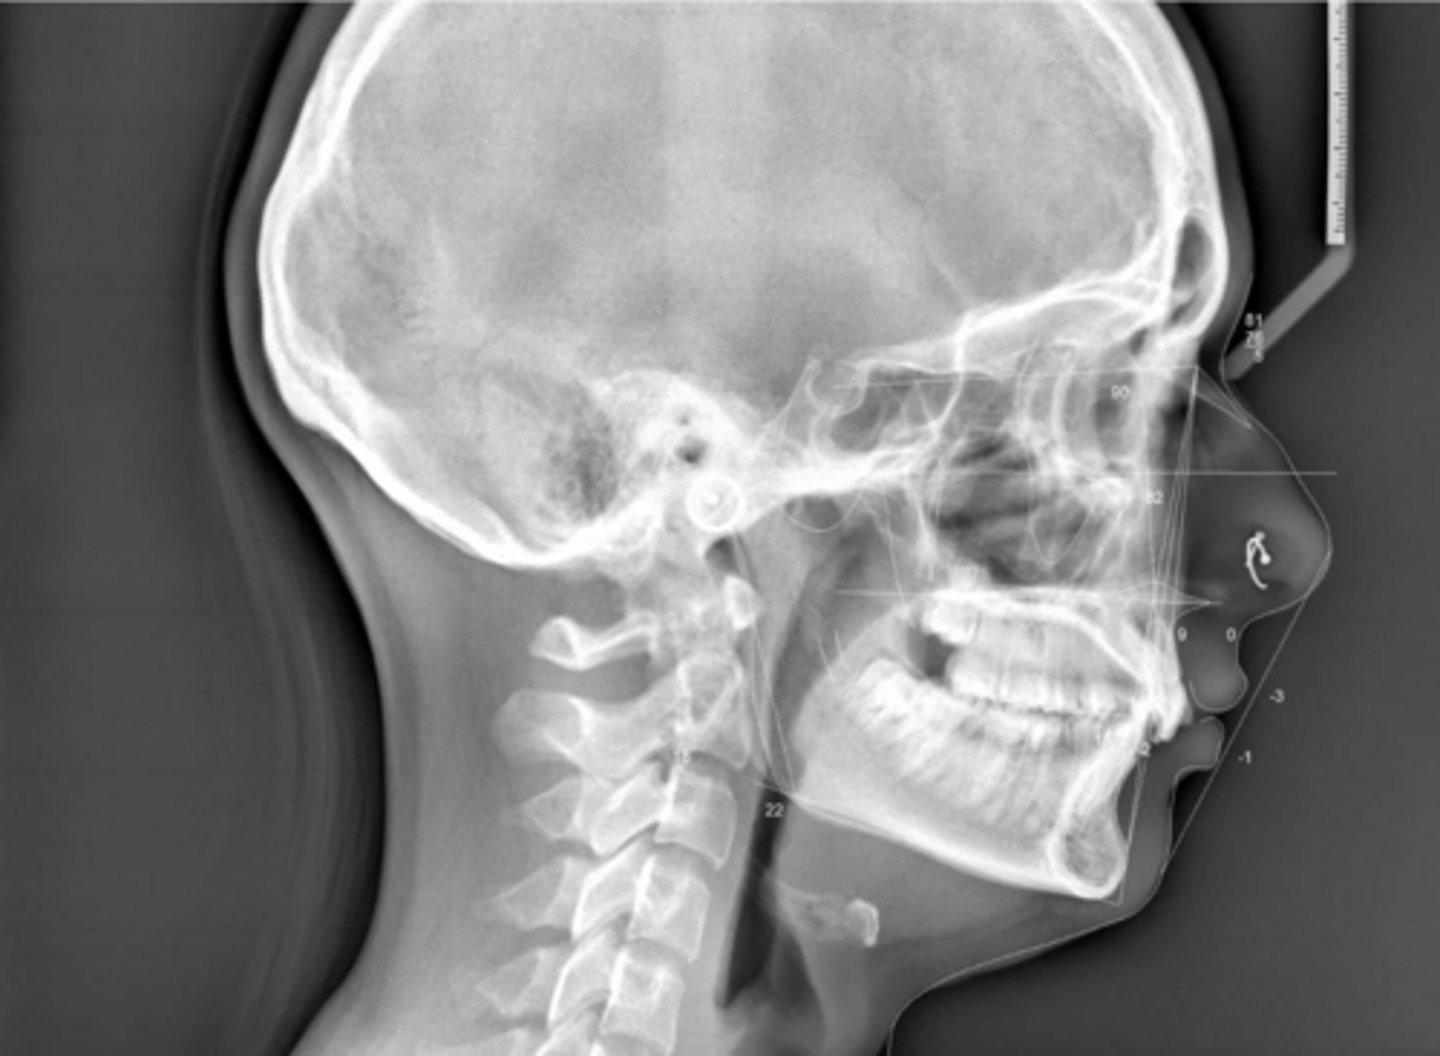

Class I

What type of skeletal malocclusion is this patient?

Normodivergent

Are the hyper-, hypo-, o normo- divergent?